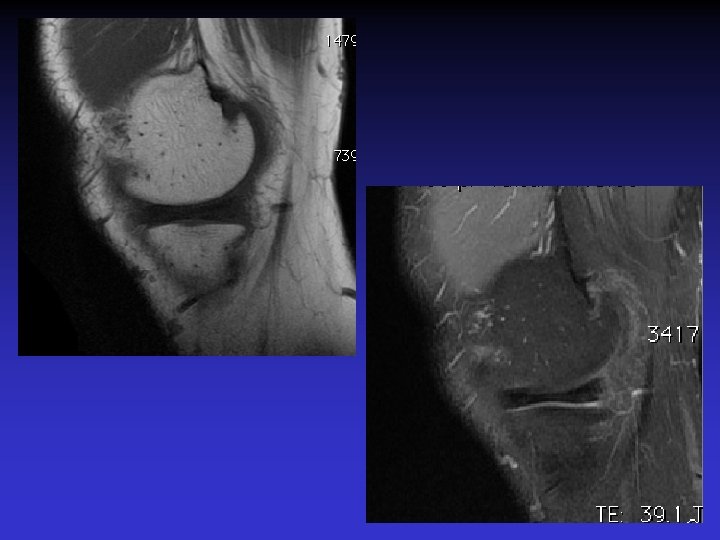

GEODES SYNOVIALES • En regard des zones d’insertion fémorale et / ou tibiale • Hypo TI Hyper T 2 • Rehaussement possible après Gado IV

GADO